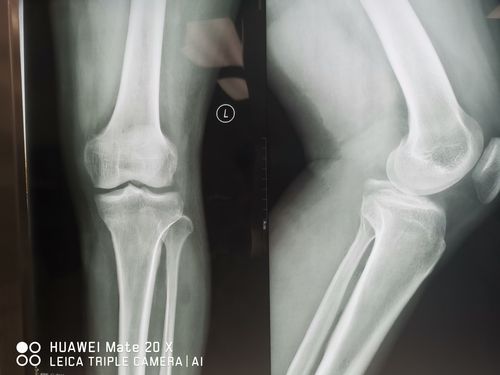

膝关节髁间棘骨折图片

膝关节髁间棘骨折图片,胫骨髁间骨折图片

胫骨髁间棘撕脱骨折

胫骨髁间骨折图片

胫骨髁间棘骨折图片

膝关节胫骨髁间棘图片

正常膝关节髁间棘图片

胫骨髁间棘图片

胫骨平台髁间棘图片

胫骨髁间棘